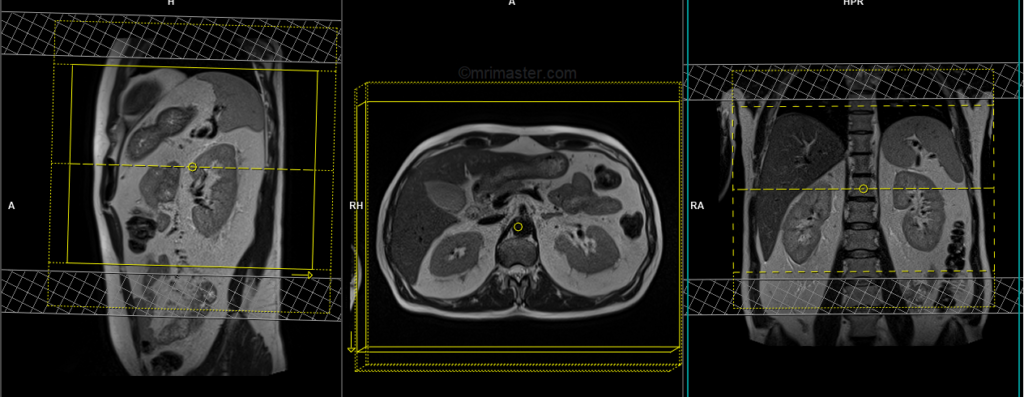

DWI epi 3 scan trace axial 3mm free breathing

Plan the axial slices on the coronal free-breathing localizer; angle the positioning block perpendicular to the thoracic vertebra. Check the positioning block in the other two planes. An appropriate angle must be given in the sagittal plane, perpendicular to the long axis of the kidney. Slices must be sufficient to cover both adrenals from the diaphragm down to the lower pole of the kidneys. Phase oversampling must be used to avoid wrap-around artifacts. Using a saturation band on the top and bottom of the block will help reduce artifacts from vascular pulsation and breathing. Instruct the patient to take shallow breathing during the acquisition.

Parameters

TR 6000-7000 | TE 90 | IPAT ON | NEX 3 5 8 | SLICE 3 MM | MATRIX 192X192 | FOV 200-250 | PHASE R>L | GAP 10% | B VALUE 0 |